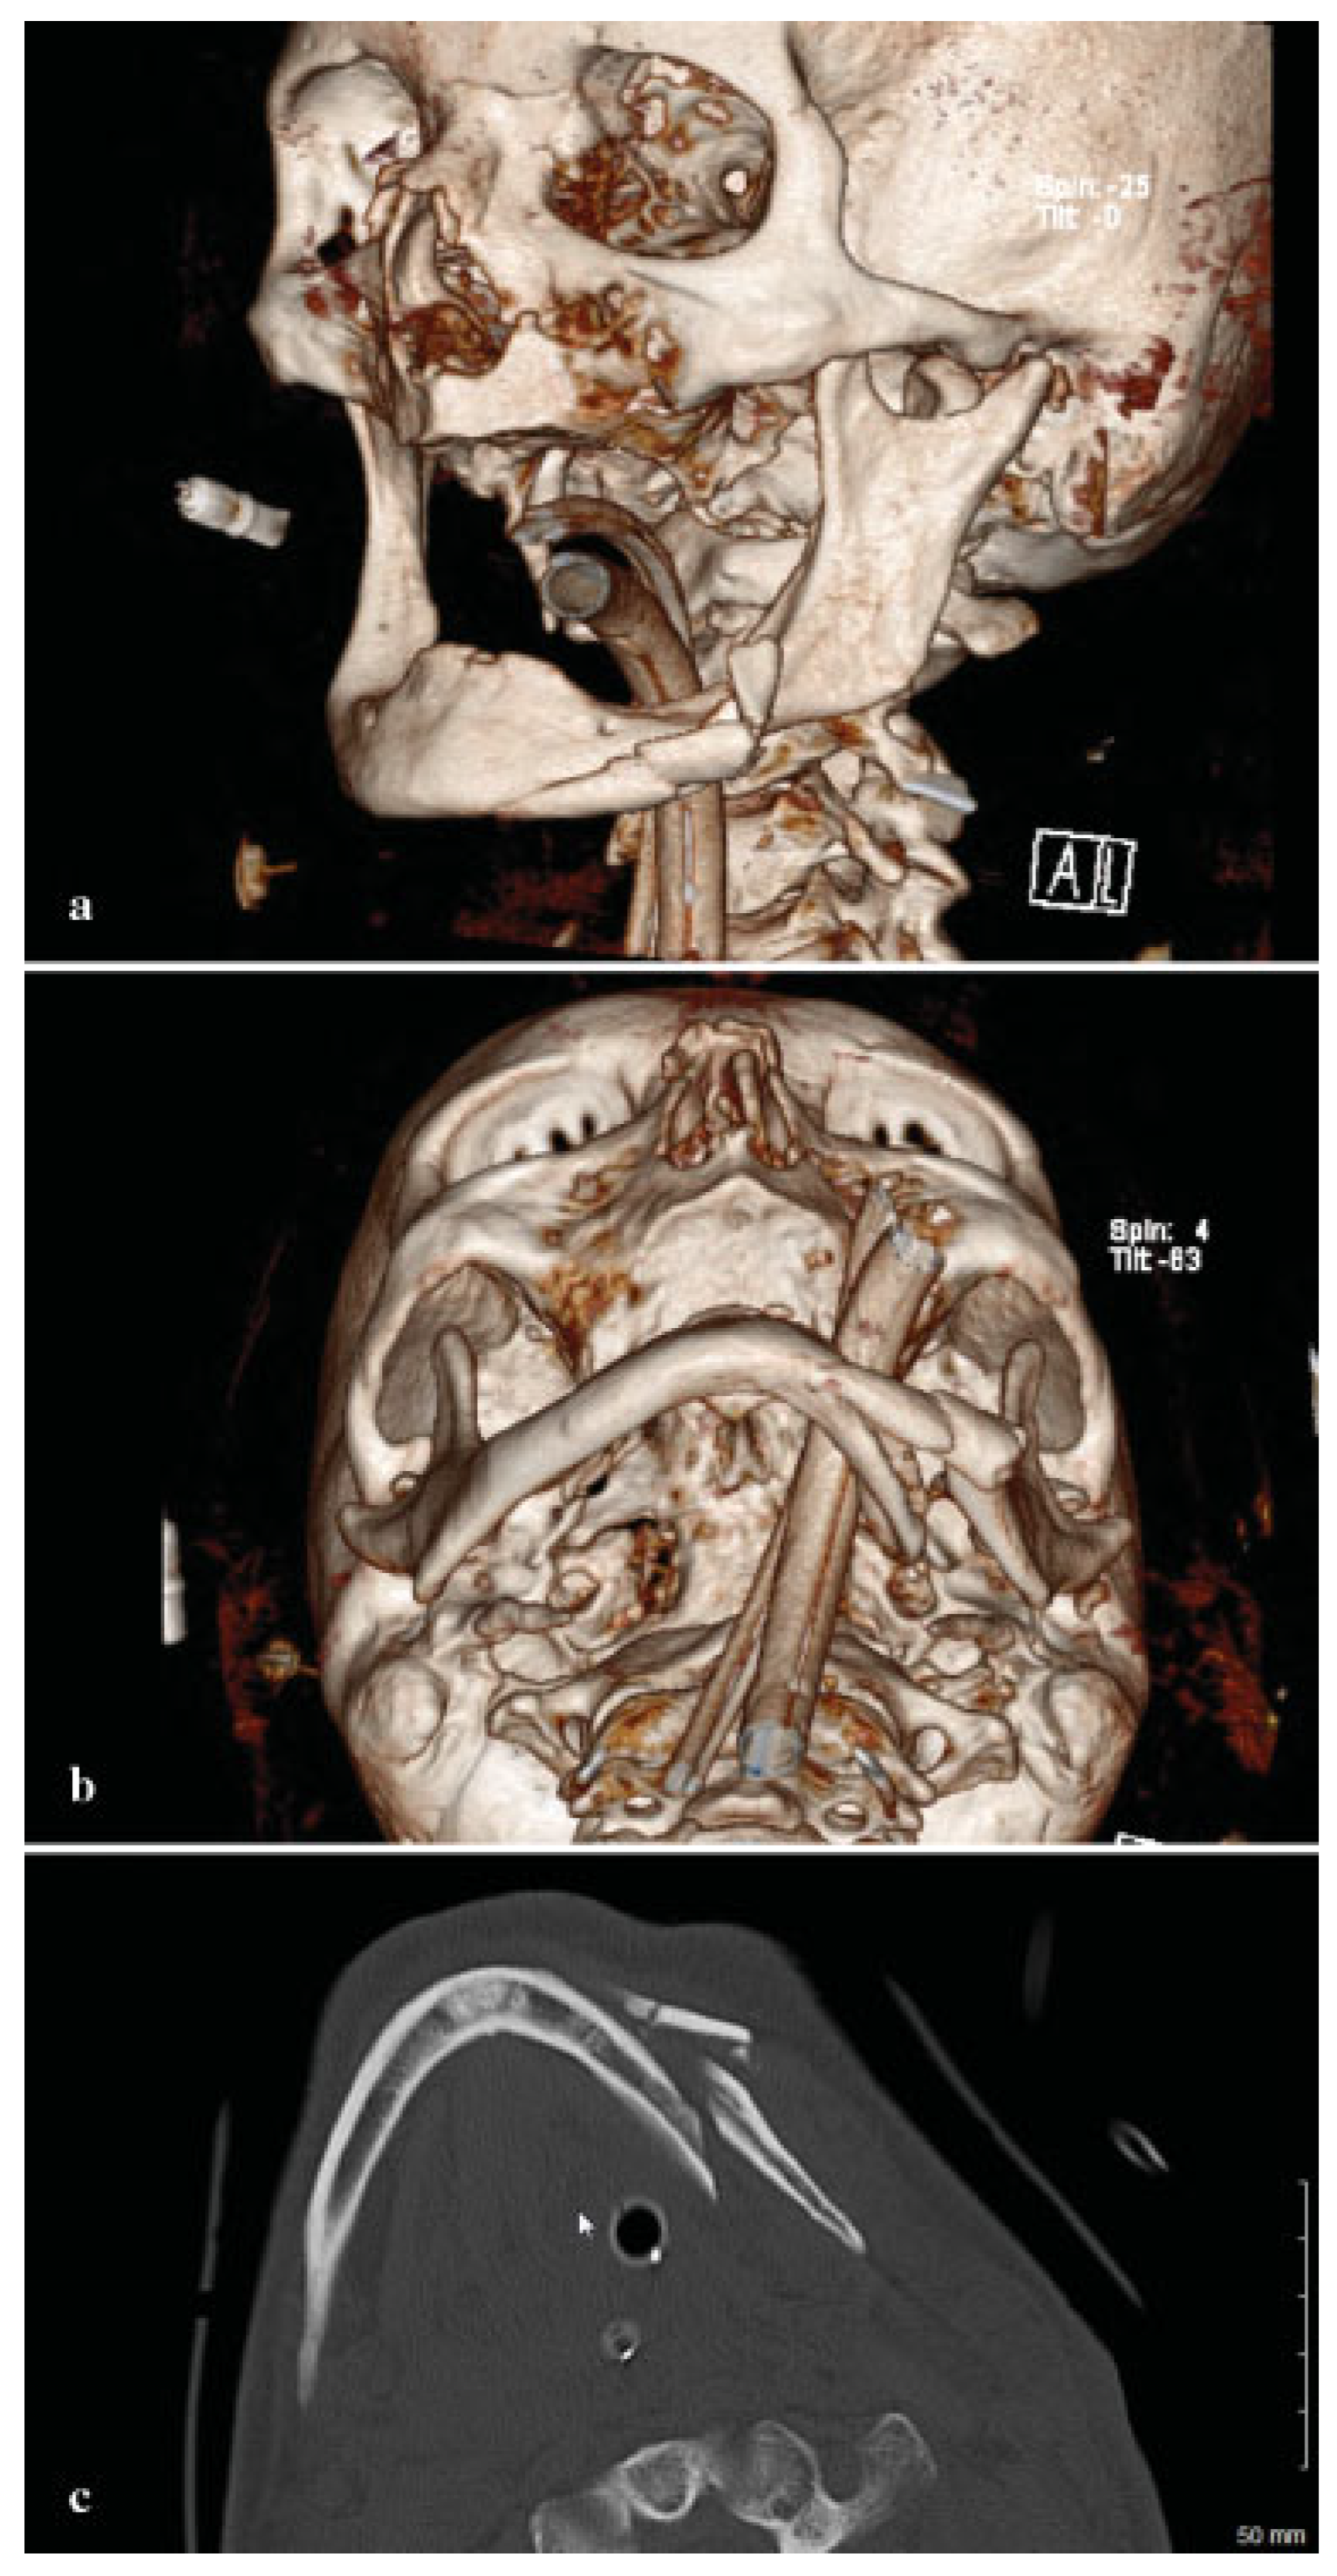

Owing to the significant injury to the anterior and posterior column of the cervical spine, a fusion was performed of C5–T1. Prior to surgery, he was kept in a cervical spine collar. To minimize the time in the operating room (OR) and manipulation of the displaced, atrophic mandible, his initial CT scans were used to fabricate a model to facilitate the correction of the complex mandible fracture. Turnaround time was 5 days. Using three-dimensional (3D) software for VSP (Materialize, Plymouth, MI), the midline of the larger segment of the mandible was aligned with the midline of the maxilla (Figure 2a,b). A mirror image was created using the opposing uninjured mandibular body (Figure 3a,b). A stereo-lithographic model was fabricated facilitating the preoperative bending of a 2.5-mm reconstruction plate, based on the virtually planned model (Figure 4). The plate was contoured to the model the evening before surgery.

Figure 2. (a) Preoperative submental image prior to manipulation. (b) Midline of mandible aligned with midline of the maxilla.

Figure 3. (a) A mirror image as seen from frontal. (b) Mirror image as seen from submental vertex.